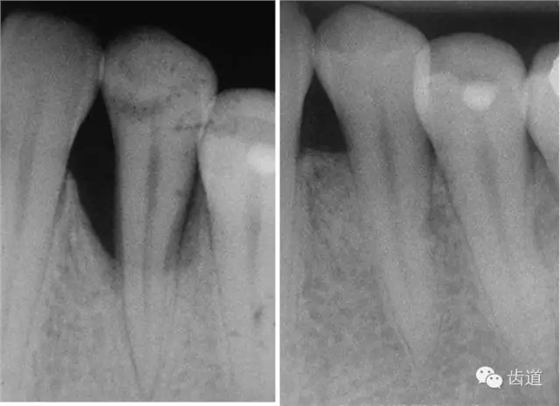

1、垂直型骨缺損:垂直性吸收形成的骨下袋,三壁袋和二壁袋的效果好,一壁袋的效果最差;

2、根分叉病變:II度或III度根分叉病損,II度效果最好;

如術(shù)區(qū)患牙無(wú)咬合創(chuàng)傷;為垂直性骨吸收且在III度以內(nèi);殘留骨壁數(shù)目多(三壁骨下袋);骨缺損窄而深(角度<250°,深度>3mm);牙齦組織較寬且厚度>1mm(抗張強(qiáng)度大及血供充分)時(shí);則臨床附著水平和骨量增加顯著。另外,根據(jù)病損牙位的特征(前牙、后牙、鄰間隙、根分叉等)選擇不同形狀、大小的屏障膜也很重要。

一般而言,不可吸收性膜的硬度較可吸收性膜高,其支架作用更強(qiáng)。因此在較寬的病損區(qū)(X線顯示角度大)或缺乏解剖結(jié)構(gòu)支持(如二壁骨缺損)時(shí),可選用不可吸收性膜;對(duì)于窄而且有支持的病損區(qū)(如三壁骨缺損),則應(yīng)用可吸收性膜更為有利。雖然各種膜材料的臨床療效無(wú)明顯差別,但如果聯(lián)合應(yīng)用植骨材料時(shí),選用可吸收性膜則僅需一次手術(shù),損傷小,操作也便利。